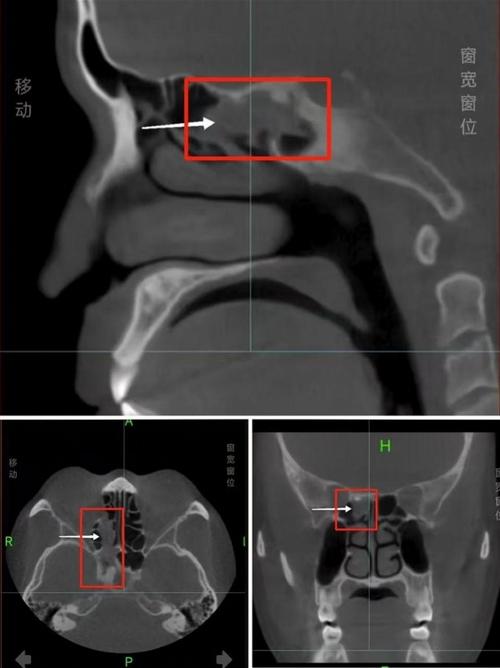

据悉,这位男士多年来的鼻窦炎症状反复发作,鼻塞、流涕和面部疼痛成为他生活中的常态,经过多次检查和药物治疗,病情始终未见明显改善,直到最近,在一次全面的鼻部检查中,医生意外发现其鼻腔内有一异物。

经过细致的手术操作,医生成功从患者鼻腔中取出了一根长达3厘米的树枝,经过分析,这根树枝可能是多年前患者不慎吸入鼻腔的,随着时间的推移,树枝在鼻腔内并未被自然排出,而是引发了长期的炎症和感染,导致鼻窦炎症状反复发作。